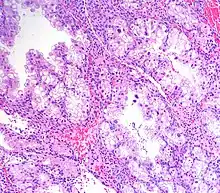

Micrograph showing Arias-Stella reaction in endometrium

Arias-Stella reaction, also Arias-Stella phenomenon, is a benign change in the endometrium associated with the presence of chorionic tissue.[1]

Arias-Stella reaction is due to progesterone primarily. Cytologically, it resembles a malignancy and, historically, it was misdiagnosed as endometrial cancer.[1]

It is characterized by nuclear enlargement and may also have any of the following: an irregular nuclear membrane, granular chromatin, centronuclear vacuolization, and pseudonuclear inclusions.[1]